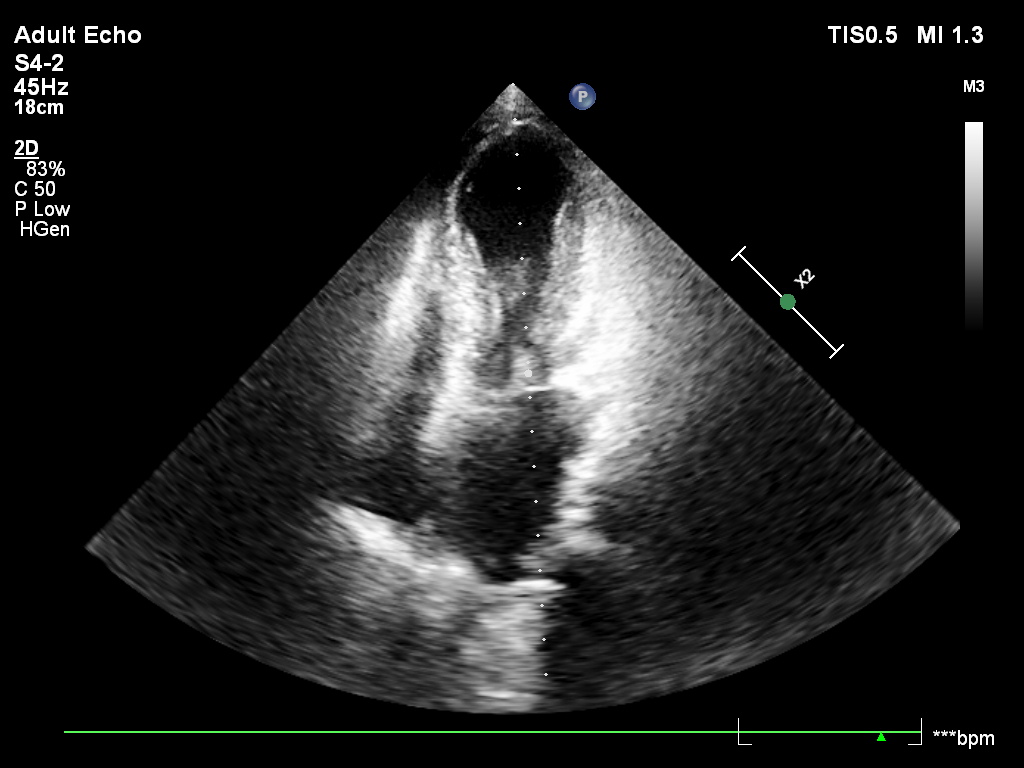

w EKG : tachykardia zatokowa, niezupełny blok prawej odnogi pęczka Hisa, fragmentacja zespołów QRS w odprowadzeniu II,III,aVF, niewielkie wklęsłe uniesienie odcinka ST w III, aVF, V5 i V6), odstęp Qtc w normie, a przede wszystkim echo serca , które wskazywało na Tako-tsubo. Rozpoznanie potwierdzono w koronarografii.

The diagnostic pitfall was the absence of a clear stressor, no chest pain, and markedly elevated D-dimers , which could initially suggest pulmonary embolism. However, further tests revised the diagnosis: elevated Troponins (966ng/l), ECG (sinus tachycardia , incomplete right bundle branch block, fragmented QRS complexes in leads II,III,aVF, slight ST-segment elevation in leads III,aVF, V5 and V6, normal Qtc interval ), and most importantly, echocardiography , which indicated Tako-tsubo cardiomyopathy . The diagnosis was confirmed by coronary angiography.